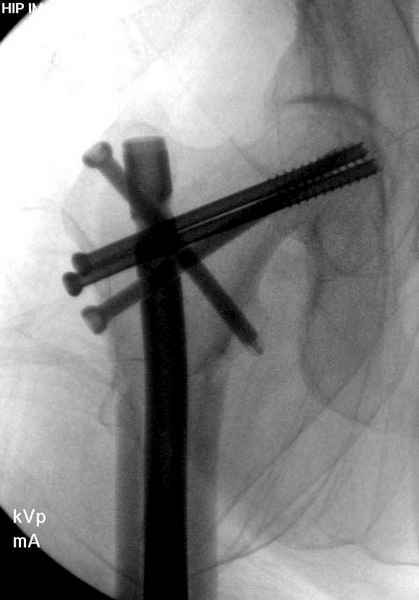

Профилактику дальнейшего раскола неполного перелома шейки провели тремя канюлированными шурупами.

Наверное речь идет насчет parallel guide из набора. Применяем по возможности всегда, но,

как видно на снимке, не всегда получается

паралельно.

Такие несмещенные переломы обычно для молодых резидентов, и бывают технические неточности, но в этом случае посчитали фиксацию адекватной.

Соблюдая правила, многократными попытками можно

увеличить риск стрессового перелома латерального

кортекса.